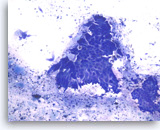

Adenocarcinoma, poorly differentiated,

Pancreas FNA, Cell Block.

Large pleomorphic tumor cells are present singly or in small stratified groups with irregular glandular lumina. Necrosis is present.

40X

Adenocarcinoma, poorly differentiated,

Pancreas FNA, Cell Block.

Large pleomorphic tumor cells are present singly or in small stratified groups with irregular glandular lumina. Necrosis is present.

40X